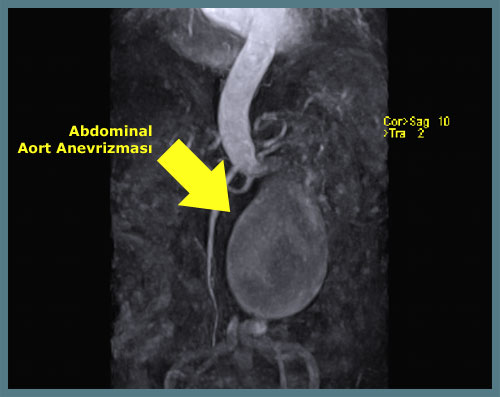

Additional diagnostic methods such as CT, MRI, and angiography may be used to plan treatment. These identify the size (the most critical factor in treatment), location, and relationships to surrounding organs. Angiography is not usually required for open surgery planning but is recommended for endovascular repair.

The presence of an aneurysm does not always require surgery. The decision is based on the aneurysm’s diameter and symptoms. The diameter is the most important factor, as rupture risk increases with size. Surgery is generally recommended when the diameter exceeds 5.5 cm (about the size of a large lemon). If the aneurysm is smaller but causing pain or rapidly growing, surgery may also be necessary.